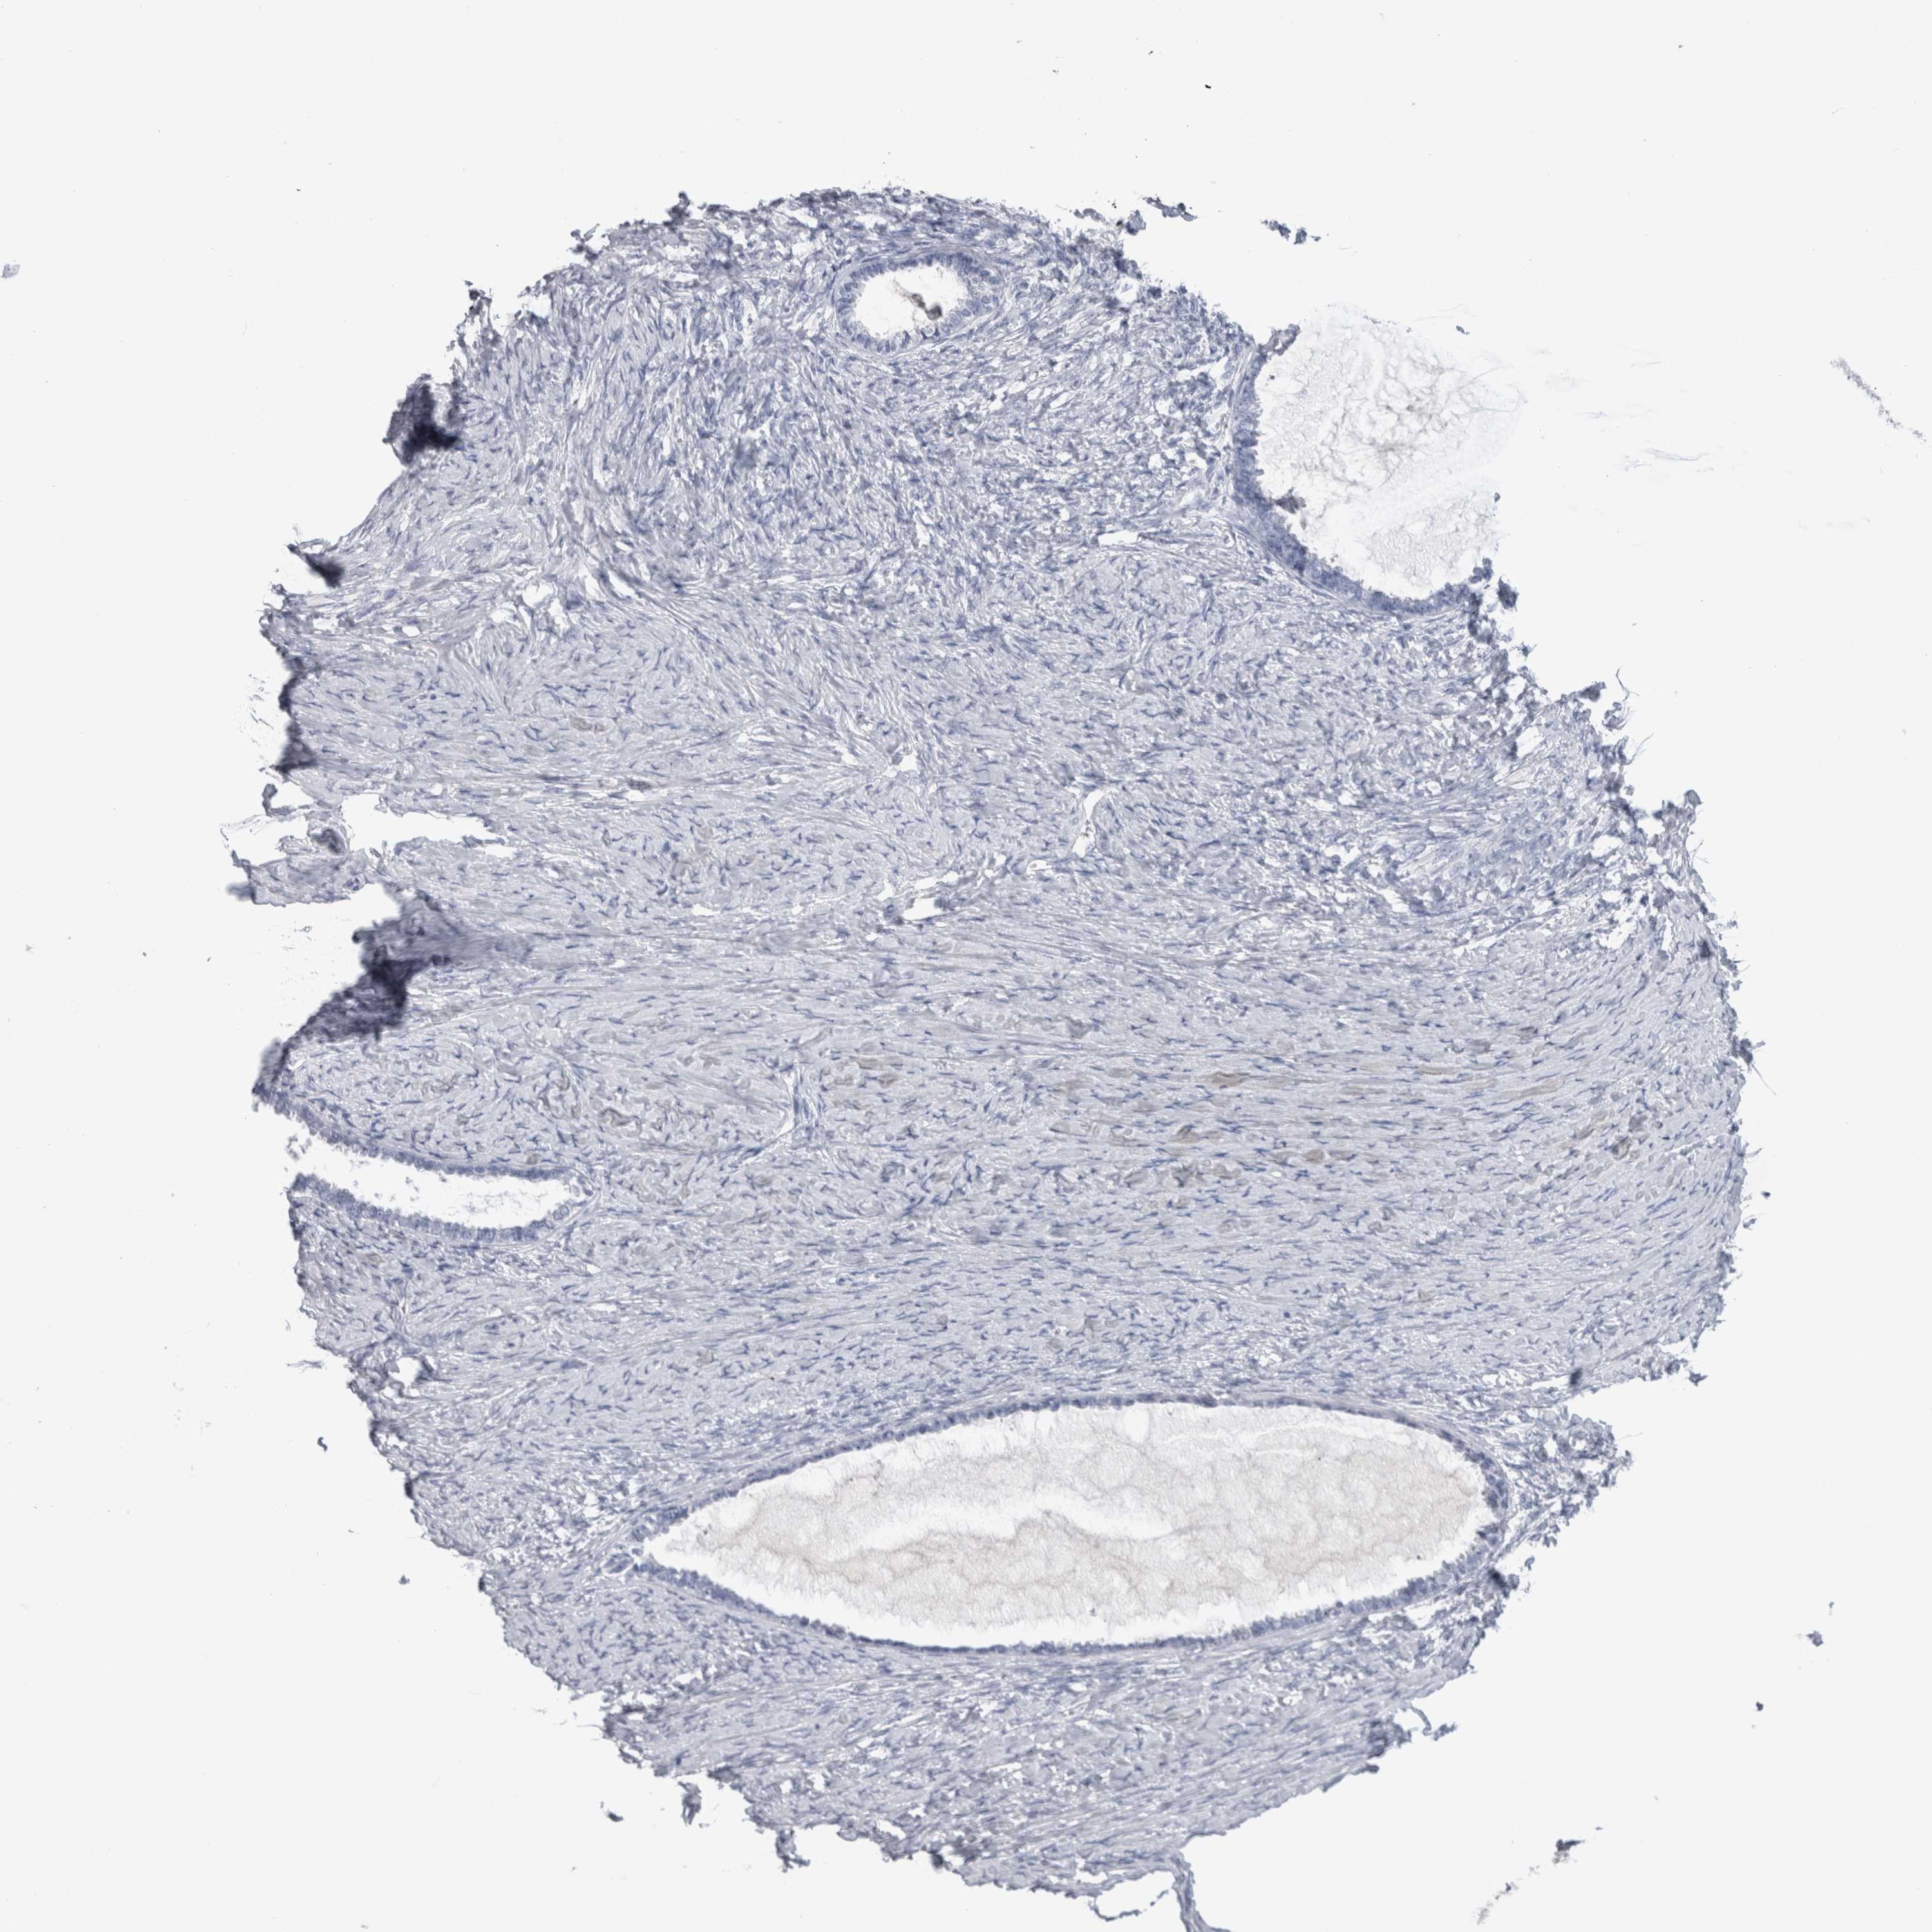

OVARIAN CANCER - Protein expressioni

A mouse-over function shows sample information and annotation data. Click on an image to view it in a full screen mode. Samples can be filtered based on level of antibody staining by selecting one or several of the following categories: high, medium, low and not detected. The assay and annotation is described here.

Note that samples used for immunohistochemistry by the Human Protein Atlas do not correspond to samples in the TCGA dataset.

Antibody stainingi

Antibody staining in the annotated cell types in the current human tissue is reported as not detected, low, medium, or high, based on conventional immunohistochemistry profiling in selected tissues. This score is based on the combination of the staining intensity and fraction of stained cells.

Each image is clickable and will lead to virtual microscopy that enables deeper exploration of all samples and also displays staining intensity scores, fraction scores and subcellular localization as well as patient and tissue information for each sample.

Antibody HPA024426

Antibody CAB007057

Cystadenocarcinoma, serous, NOS

Carcinoma, endometroid

Cystadenocarcinoma, mucinous, NOS

Carcinoma, NOS